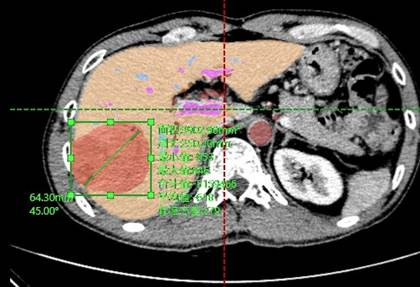

Más de 100 hospitales ya han desplegado Hisense CAS, un sistema de cirugía asistida que mejora el tratamiento médico

Hisense CAS (Computer-Assisted Surgery), capaz de ofrecer a los médicos un sistema de análisis cuantitativo y una reconstrucción de imágenes médicas eficiente, precisa y simple, es la principal aportación de la marca a la medicina moderna. Una solución completa que ayuda a los profesionales sanitarios en operaciones abdominales, de órganos como el hígado, la vesícula biliar, el páncreas o los riñones, y fundamental para el diagnóstico prematuro de enfermedades como el cáncer.